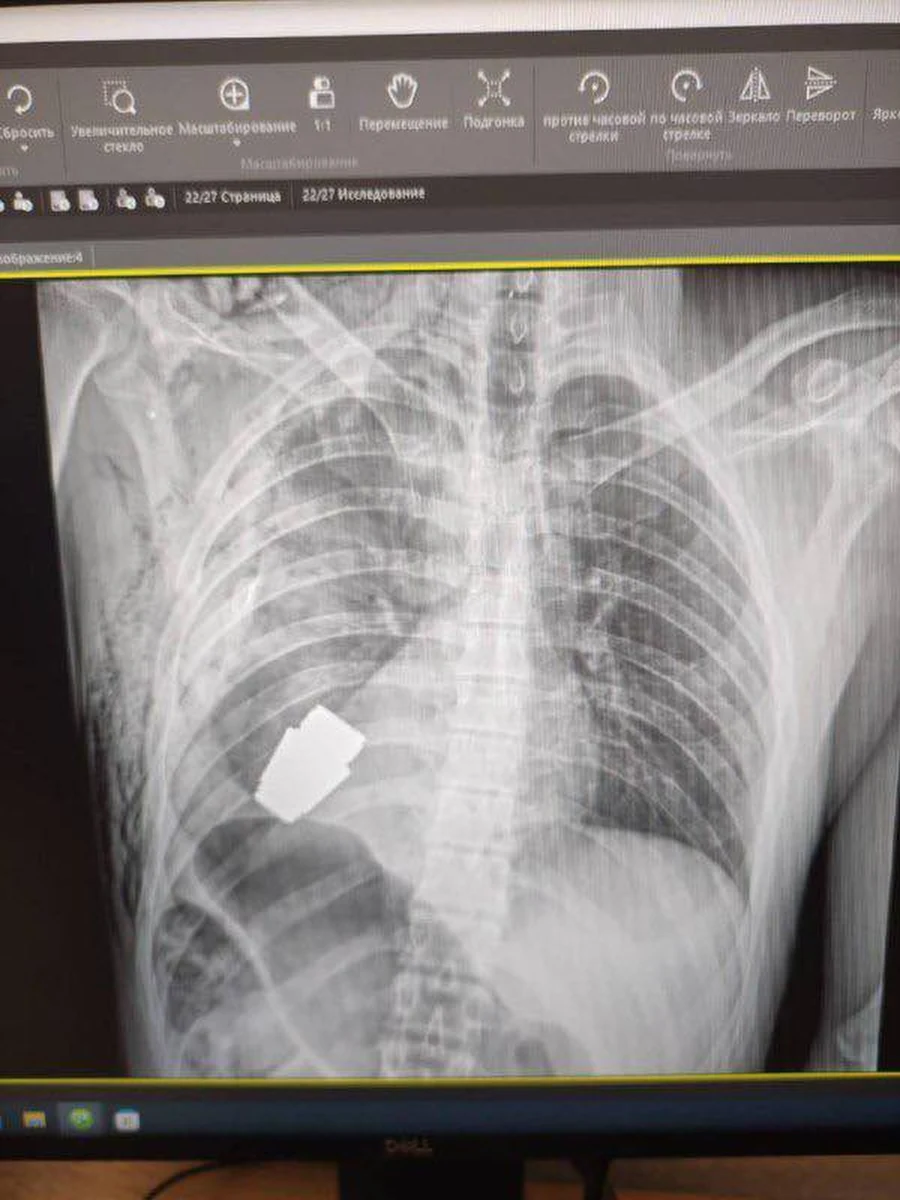

Opublikowane przez nią fotografie pokazują spory pocisk widoczny na zdjęciu rentgenowskim klatki piersiowej rannego żołnierza i ten sam pocisk wydobyty już przez chirurga.

Jak podkreśliła Malar, pocisk mógł eksplodować w każdym momencie, dlatego zabieg przeprowadzono bez użycia elektrokoagulacji, czyli metody, w której wykorzystywany jest niewielki przepływ elektryczny.